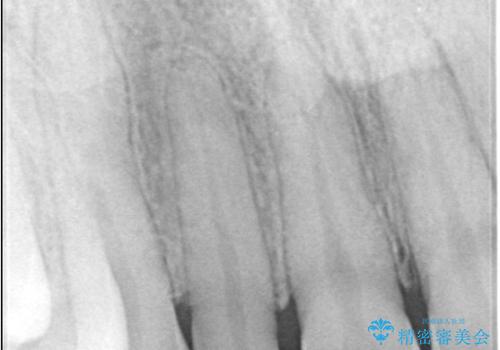

- 歯並びを矯正で整えたあと、上顎左右2番の歯(前歯の横の歯)の「矮小歯(歯が小さい状態)をオールセラミッククラウンで審美修復した症例です。

矯正によって歯並びはきれいに整いましたが、前歯全体のバランスをより自然で美しく仕上げるため、上顎左右2番にオールセラミッククラウンによる審美修復を行いました。

矮小歯はもともと歯が小さいため、削る量を最小限に抑えた負担の少ない治療が可能です。